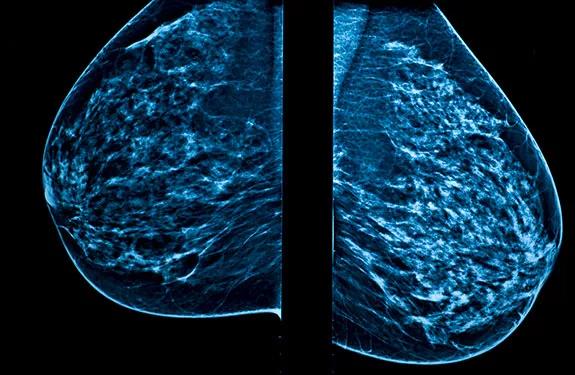

American College of Physicians Issues New Breast Cancer Screening Guidelines

Guidelines weigh potential harm and benefit of breast cancer screenings, with some discrepancy among professional societies

The American College of Physicians has issued new screening guidelines for women of average risk of developing breast cancer.

The guidelines suggest that, for the average-risk woman under 50 years old who does not have breast symptoms, the potential for harm in breast cancer screenings outweigh the benefits. The guidelines emphasize the importance of beginning discussions about breast cancer risks and screening with patients at age 40. These guidelines recommend that average-risk women have mammogram screenings biennially between the ages of 50 and 74. In average-risk women who are 75 or older, with a life expectancy of 10 years or less, the recommendation is to discontinue screening for breast cancer.

The new statement differs slightly from guidelines set forth by the American Cancer Society, which still recommend average-risk women begin mammogram screenings at age 45 and continue them annually until age 54, and then every other year afterward.

The new guidelines are based on research indicating that mammograms performed every other year reduce the potential for false-positive test results, over-diagnosis, over-treatment and radiation exposure, among other factors.